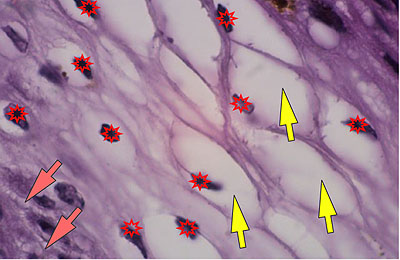

Photo 6 (Hémalun Eosine X 400) : vue rapprochée au fort grossissement d’une crête épithéliale

émanant de la gaine épithéliale externe d’un follicule pileux (portion infundibulaire).

L’aspect filiforme et longiligne s’accompagne d’une certaine perte de polarité des cellules basales

dont le grand axe cytoplasmique devient parallèle au grand axe de la crête épithéliale, au lieu

d’être perpendiculaire. La couche la plus basale perd ainsi son habituel aspect palissadique.

Légendes de la Photo 6 :

- Triangles bleus clairs : contours de crêtes épithéliales allongées, filiformes, ramifiées et branchues, peuplées de cellules basales hyperbasophiles, émanant de la gaine épithéliale externe des infundibula folliculaires

- Flèches rouge : parakératose folliculaire

- Étoiles rouge pleines : Le derme est faiblement à modérément inflammatoire (infiltrat mononucléé)

- Étoiles rouges claires : angiectasie des capillaires sanguins

- Ronds marron :tiges pilaires

- Flèches orange : mélanocytes

- Flèches jaune : mélanophages